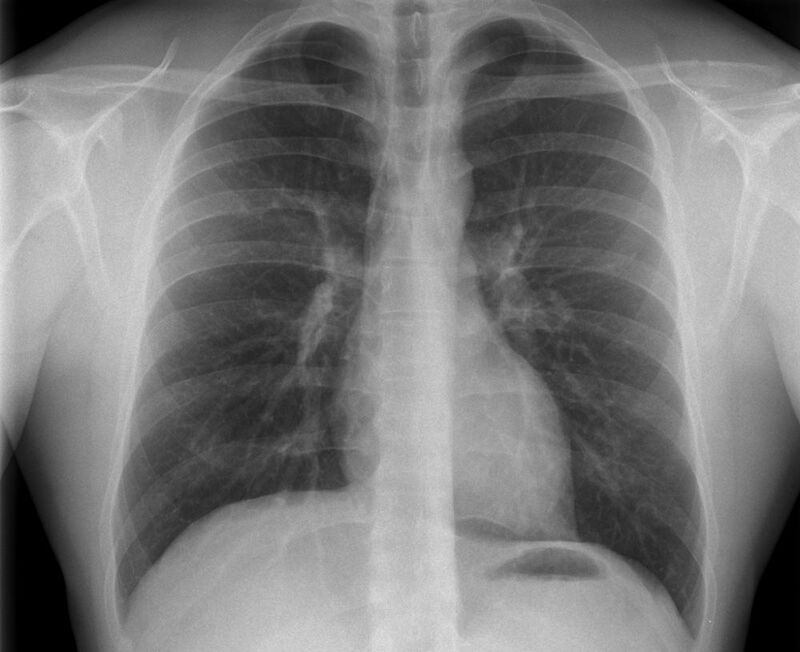

Konventionelles Röntgen

Der Begriff Röntgen, oder auch Röntgendiagnostik bezeichnet ein Verfahren in der Radiologie, bei dem von einer Röntgenröhre elektromagnetische Wellen (Röntgenstrahlen) durch die zu untersuchende Körperregion des Patienten gesendet werden. Je nach Dichte der Gewebeart des Körpers (z.B. Knochen oder Lunge) werden die Röntgenstrahlen im Körper unterschiedlich stark abgeschwächt. Ein digitaler Detektor empfängt dann die Röntgenstrahlen, die in abgeschwächter Form den Körper wieder verlassen haben. Daraus wird das Röntgenbild erzeugt.

Die Röntgenuntersuchung ist weiterhin eine unverzichtbare Basisdiagnostik. Viele Fragen können in der medizinischen Diagnostik mit einer konventionellen Röntgenaufnahme geklärt werden.

Durch den Einsatz neuester volldigitaler Röntgentechnik wird die Strahlendosis auf niedrigstem Niveau gehalten.